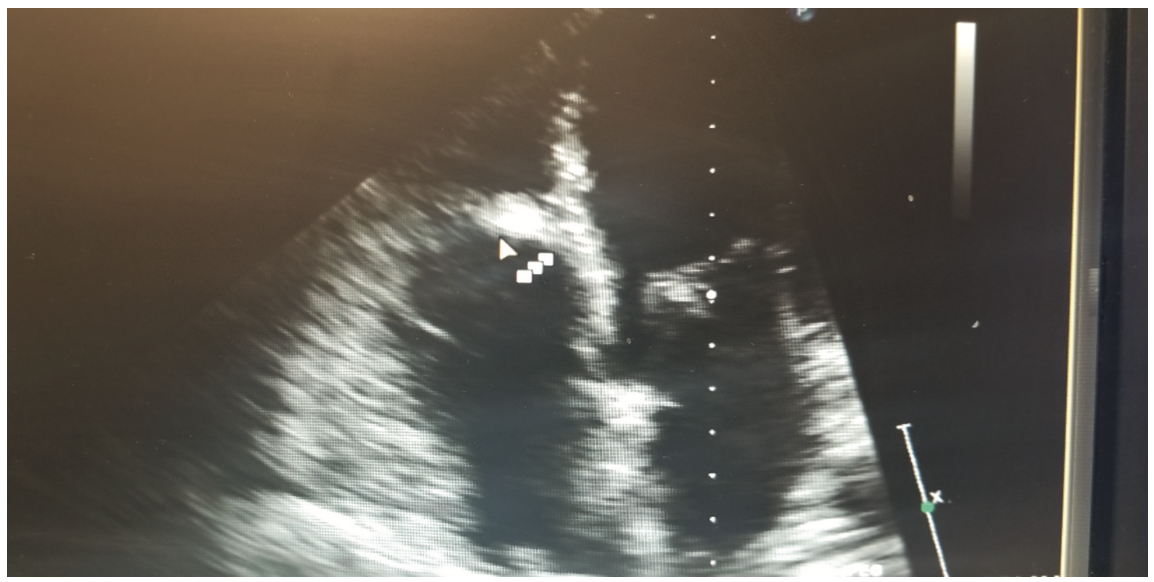

This is a 58-year-old female with a history of tuberous sclerosis. Transthoracic echocardiogram images demonstrated a heterogeneous mass in the mid right ventricle attached to the septum and the moderator band (Figures 1-6). The mass looked similar to what was seen on a transthoracic echocardiogram from a year prior.

One of the major differentials for this mass was thought to be cardiac rhabdomyoma, given the patient’s history of tuberous sclerosis with known renal angiomyolipomas. Cardiac rhabdomyomas are usually associated with tuberous sclerosis complex, which is a genetic disorder characterized by hamartomas in multiple organs. Rhabdomyomas may develop at any location in the heart, but the most common locations are ventricular and septal walls.